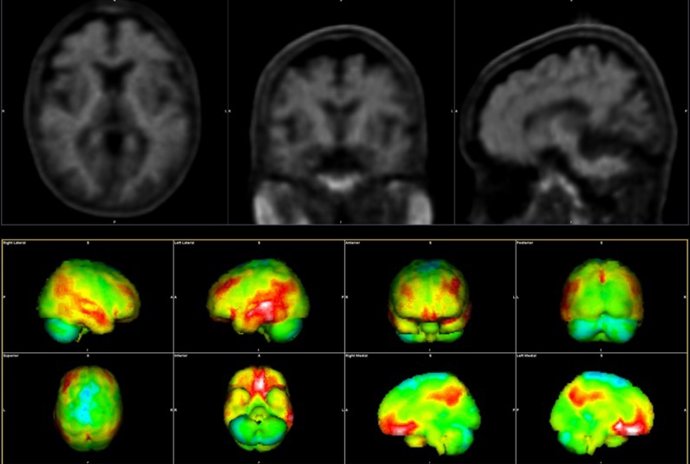

Hallazgos de la PET en la enfermedad de Alzheimer: PET con amiloide en un paciente anciano con síntomas de EA.

Hallazgos de la PET en la enfermedad de Alzheimer: PET con amiloide en un paciente anciano con síntomas de EA. - WENTWORTH-DOUGLAS HOSPITAL, DOVER, NEW HAMPSHIRE

Asimismo, la compañía trabajará también en reducir las barreras técnicas, operativas y económicas que limitan el acceso a técnicas de neuroimagen avanzadas en Europa, liderando el desarrollo y la implementación clínica de soluciones de RM y PET, escalables más allá de los centros altamente especializados. En resonancia magnética, esto podría incluir tecnologías de imanes 'DryCool' compactas y sin helioi, flujos de trabajo asistidos por IA, reconstrucción de imágenes mejorada y protocolos acelerados que reduzcan significativamente los tiempos de exploración.